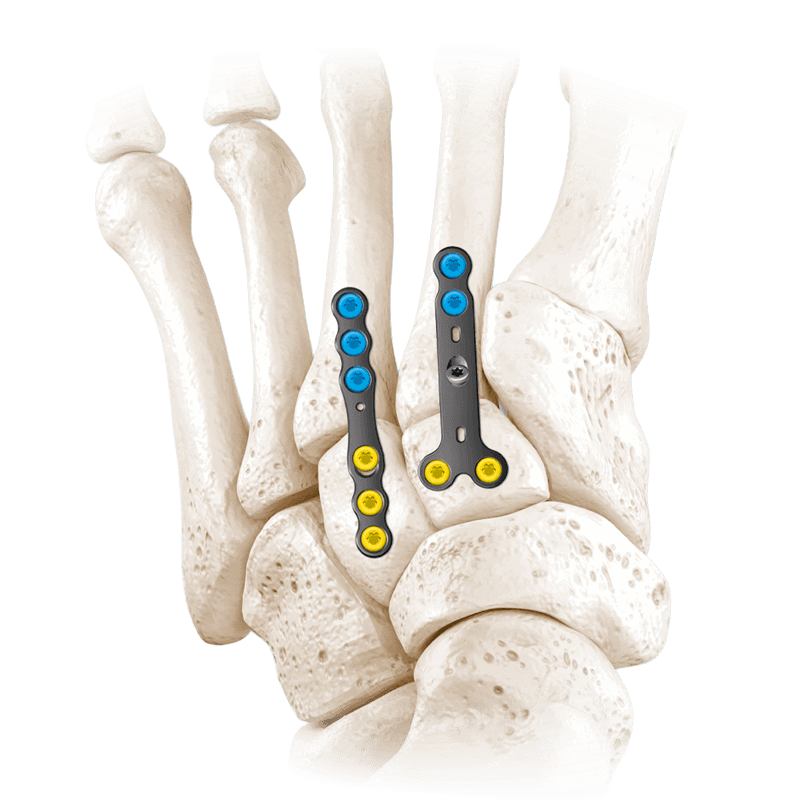

Fixation Devices - Plating Systems

CoLink® PCR Carbon Fiber Plating System

Carbon Fiber Reinforced PEEK is the new revolution

CoLink®2 Compression Plating System

Tapered Compression Slot Technology creates mechanical compression across the fusion site

CoLink® Mini Dynamic Compression Plating System

Comprehensive plating system designed to address a variety of fractures and fusions

CoLink® Mfx Midfoot Plating System

Designed to address fractures, fusions, and osteotomies of the midfoot